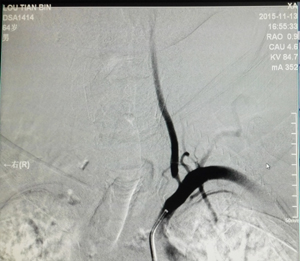

图为左侧椎动脉起始段狭窄手术后DSA 图为右侧椎动脉起始段狭窄手术后DSA 拷贝